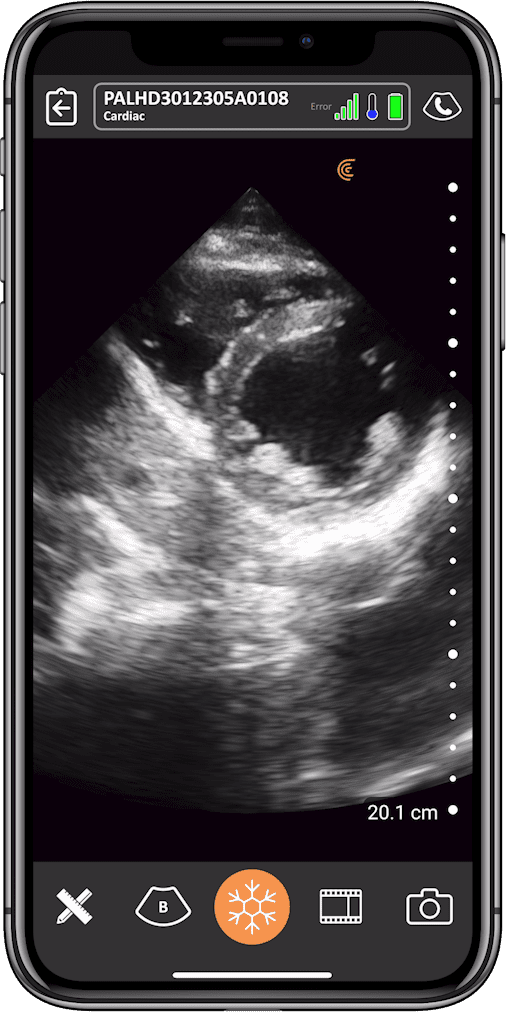

Cardiac POCUS: Coronary Artery Disease for the Non-Cardiologist

Emergency physician and ultrasound educator Dr. Tom Cook teaches how to accurately assess left ventricular wall motion in the presence of coronary artery disease, for improved patient management.

In this 1-hour webinar, you will learn how to extend your cardiac POCUS repertoire to identify regional abnormalities in contractile function of the left ventricular walls in patients with suspected acute coronary artery syndromes (ACS) or older infarcts. You’ll learn:

As always, Dr. Cook will review real cases with healthy and pathological images and video clips to help you develop the skills to generate and interpret ultrasound images on your patients. Join this free webinar to gain practical knowledge you can use on your next day in the ER, hospital ward, or intensive care unit.